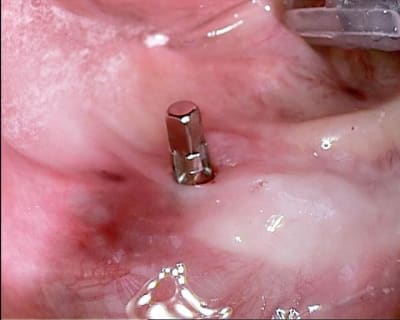

Un cas qui va sans doute prêter à discussions, juste pour montrer que la technique MIMI (non invasive) peut donner des résultats de qualité et esthétiques en moins de temps qu une chirurgie dite traditionnelle.

Les deux premières photos montrent le cas d´une jeune femme ( qui malheureusement s est fait retiré toutes les dents à l´étranger....).Ce cas a pu être terminé deux semaines après l´implantation.

Les forets utilisés ont 3 faces et sont coniques (250 trs/min) permettent une condensation de l´os et un traitement minimalement invasif.